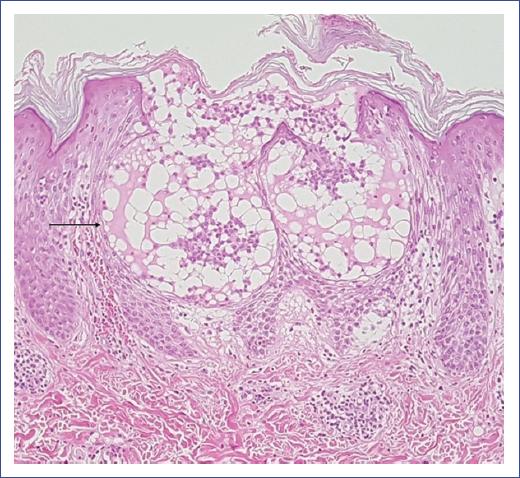

Figure 2 Acute generalized exanthematous pustulosis. Subcorneal blister in the stratum of Malpighi containing fibrin, few neutrophils, and eosinophils (arrow). Spongiosis and lymphocyte exocytosis are observed. Papillary and upper reticular dermis with mild lymphocytic inflammatory infiltrates and few eosinophils with perivascular distribution and intravascular neutrophils. Dilated capillaries with mild wall edema, some congestive with focal erythrocyte extravasation (hematoxylin-eosin stain, 10x).

Histopathology confirmed the clinical diagnosis. Usually, subcorneal or intraepidermal spongiform pustules, edema of the papillary dermis, perivascular infiltrates of neutrophils, and some eosinophils are observed (Figure 2). In addition, focal keratinocyte necrosis and leukocytoclastic vasculitis are occasionally detected17,20.